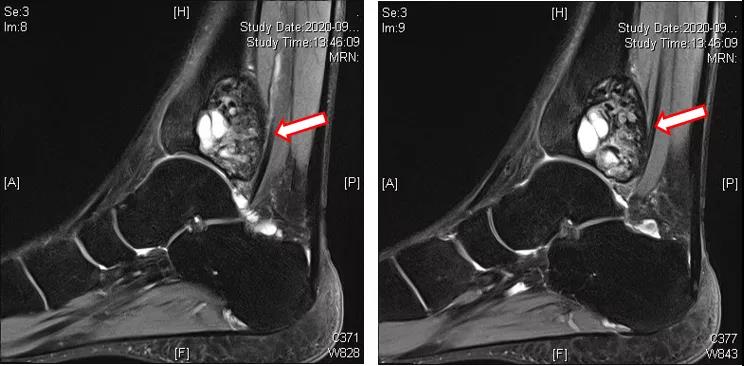

进一步完善CT检查提示:胫骨远端病变内不规则高密度影,成骨明显(图7~9)。

图7:左踝CT(地舒单抗治疗后)

图8:左踝CT(地舒单抗治疗后)

图9:左踝CT(地舒单抗治疗后)

术前应用地舒单抗三次(120mg,ih,q1w),疗效显著,复查MRI提示胫骨远端病变内T2WI高信号范围减小;CT提示病变内不规则高密度影,成骨明显。